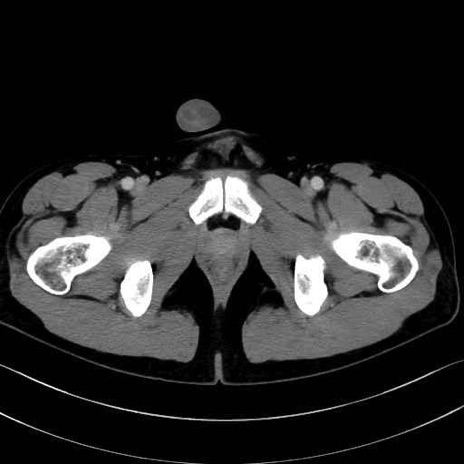

梨状筋 (Piriformis)

内閉鎖筋 (Obturator internus)

外閉鎖筋 (Obturator externus)

大腿方形筋 (Quadratus femoris)